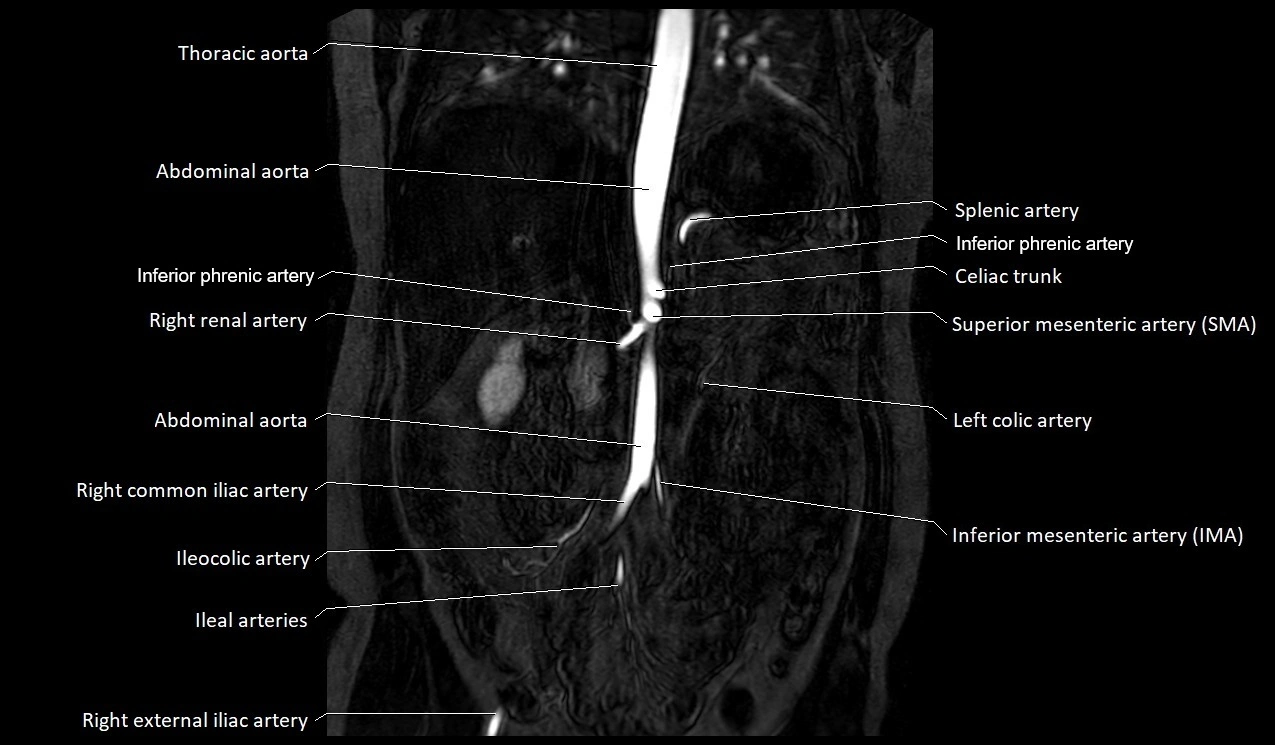

MRI Appearance

T1-weighted images:

Artery appears as a small linear hypointense flow void coursing over the superior pubic ramus

Seen within bright perivascular fat of pelvis

T2-weighted images:

Artery lumen is a signal void

In thrombosed or diseased variants, lumen may appear hyperintense relative to surrounding fat

STIR:

Fat suppression makes the artery more visible within pelvic fat

Helps identify perivascular edema, hematoma, or inflammatory changes

T1 Post-Gadolinium (with fat suppression):

Artery enhances brightly and homogeneously

Useful for tracing the course, anastomoses, and presence of corona mortis

Highlights arterial wall thickening or tumor encasement if present

MRA Pelvis with Gadolinium:

Clearly delineates the origin, course, and anastomoses of the accessory obturator artery

Identifies connection with inferior epigastric artery, external iliac artery, or obturator artery

Excellent for detecting vascular variants prior to surgery

Useful in mapping pelvic vasculature in trauma, tumor embolization, or preoperative planning